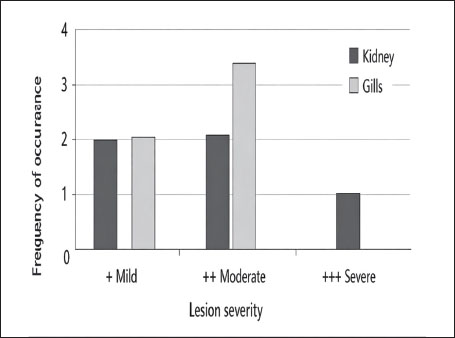

Fig. 13. Histopathology of the gills in an adult L. sceleratus showing congestion and telangiectasia of gill filament vessels (thick arrows) and lamellar dilation due to RBC accumulation (head arrows). ×40 H&E. Gill lesions were described separately for tissues with visible parasites and those without parasitic structures to improve interpretative clarity. Summary of lesionsHistopathological alterations in both kidney and gill tissues were classified using a semi-quantitative scoring system (+, ++, +++) (Fig. 14).

Fig. 14. Frequency distribution of lesion severity in the kidney and gills (+, ++, +++). Descriptive baseline data; no statistical comparisons due to lack of control. Kidney tissuesModerate tubular degeneration and Bowman’s capsule dilatation were recorded, whereas MMC proliferation was severe (+++). Vascular congestion and mild inflammation were observed. No parasitic structures were detected in kidney tissues. Observed alterations represent descriptive baseline histopathological changes. Gill tissuesModerate secondary lamellae dispersion, aneurysm dilation, epithelial hyperplasia, and edema/epithelial lifting were observed, whereas filament deformities and unidentified parasites were mild (+). Lesions were described separately for tissues with visible parasites and non-parasitized tissues to improve interpretative clarity. It should be noted that no unpolluted control group was included, and these observations represent descriptive baseline data; no causal inference regarding environmental stressors can be drawn (Table 1). Table 1. Semi-quantitative scoring of histopathological alterations in kidney and gill tissues of L. sceleratus along the Libyan coast (n=150 adult specimens).

DiscussionThe present study revealed pronounced histopathological alterations in both the kidneys and gills of L. sceleratus collected along the Libyan coast. Kidney lesions, including tubular degeneration, Bowman’s capsule dilatation, proliferation of MMCs, vascular congestion, and inflammatory infiltration, were associated with histologically detected structures, but no parasitic structures were detected in kidney tissues. These patterns are commonly reported in marine teleosts exposed to chronic environmental stressors (Ali et al., 2014; Steinel and Bolnick, 2017; Carreras-Colom et al., 2022). These lesions should be interpreted as descriptive indicators of physiological stress rather than direct evidence of chemical pollution or causality, consistent with Flores-Lopes and Thomaz (2011). Vascular abnormalities, including congestion and thickened vessel walls, were evident, which may reflect chronic circulatory disturbances or inflammatory responses rather than acute toxicity (Bernet et al., 1999; Thophon et al., 2003). Interstitial lymphohematopoietic tissue, inflammatory cell infiltration, and granulomatous formations suggest that parasitic or microbial challenges could contribute to renal lesions. Despite these histopathological changes, the sampled fish appeared healthy at capture, demonstrating the potential physiological resilience of marine teleosts. Fish kidneys possess compensatory mechanisms, and gills serve critical osmoregulatory and excretory functions, allowing survival despite structural alterations (Evans et al., 2005; Hwang et al., 2011; Hinton et al., 2018; Leone et al., 2018). Gradual development of renal lesions likely enables adaptation without acute organ failure. Gill tissues also exhibited pronounced alterations, including disorganization of secondary lamellae, club-shaped filament deformities, lamellar aneurysms, epithelial hyperplasia, and edema. These changes are consistent with chronic, sublethal tissue responses observed descriptively, without inferring specific environmental stressors or chemical toxicity (Sinha et al., 2014; Carvalho et al., 2020; Pramanik and Biswas, 2024). Unidentified parasitic structures, morphologically consistent with metazoan parasites, were observed based on histological appearance. Lesions were described separately for tissues with visible parasites and non-parasitized tissues to improve interpretative clarity (Sitjà-Bobadilla, 2008; Biller and Chagas, 2022). The proliferation of MMCs in gills reflects an immune response to tissue damage and cellular debris, reinforcing the descriptive nature of the findings. Vascular congestion and lamellar dilation due to RBC accumulation may indicate sublethal circulatory stress, but these observations are descriptive and not confirmed by physiological measurements (Triebskorn et al., 2007; Hasan et al., 2022). Moderate lesions (++), as summarized in Table 1 and illustrated in Fig. 14, were predominant, reflecting chronic, sublethal tissue responses rather than lethal injury. Overall, the kidney and gill lesions detected in L. sceleratus reflect chronic, sublethal tissue responses observed descriptively. No causal relationships with environmental stressors or chemical pollution can be inferred. Future studies incorporating water and sediment analyses, parasitological identification, and reference/control populations are recommended to strengthen the interpretation of these histopathological responses as potential biomarkers. LimitationsThis study is limited by the absence of environmental physicochemical data, the lack of a reference or control site, and the descriptive nature of the histopathological assessment. In addition, parasitic structures were not identified to species level, and quantitative prevalence metrics were not calculated. Accordingly, the findings should be interpreted as baseline descriptive observations rather than indicators of specific environmental stressors or pollution sources. ConclusionHistopathological examination of the kidneys and gills of L. sceleratus revealed tissue-level changes that serve as descriptive baseline data. Moderate to severe alterations were observed, including tubular degeneration, MMC proliferation, vascular congestion, secondary lamellae disorganization, and epithelial hyperplasia. No parasitic structures were detected in kidney tissues, while parasitic structures were observed only in some gill tissues and described separately. Despite these alterations, the species exhibits physiological compensation mechanisms, including renal adaptive responses and gill-mediated osmoregulation, supporting resilience under sublethal stress conditions. These findings are descriptive and should not be interpreted as direct evidence of environmental contamination or causation. All observations represent baseline histopathological data, intended to support future comparative and environmentally integrated studies rather than establish causal relationships. AcknowledgmentsThe authors sincerely thank the staff of the Pathology and Clinical Pathology Department (Faculty of Veterinary Medicine, Omar Al-Mukhtar University) and the Zoology Department (Faculty of Science, Omar Al-Mukhtar University) for their valuable support. Conflict of interestThe authors declare that there is no conflict of interest. FundingThis research received no specific grant. Authors' contributionsEda M. A. Alshailabi and Sana A. A. Mohammed contributed to the project idea and design, and Sana A. A. Mohammed and Ismail M. Hdud executed the study. Eda M. A. Alshailabi drafted and wrote the manuscript. Sana A. A. Mohammed and Samia M. Efkeren reviewed the manuscript critically. All authors have read and approved the final manuscript. Data availabilityAll data supporting the findings of this study are available within the manuscript. ReferencesAli, A.O., Hohn, C., Allen, P.J., Ford, L., Dail, M.B., Pruett, S. and Petrie-Hanson, L. 2014. The effects of oil exposure on peripheral blood leukocytes and splenic melano-macrophage centers of Gulf of Mexico fishes. Mar. Pollut. Bull. 79(1–2), 87–93; doi:10.1016/j.marpolbul.2013.12.036 Alshailabi, E., I.Al-Zail, N. and Abraheem, R. 2023. The effects of cigarette smoke on the epididymal tissues in adult male albino rats and the ameliorative effect of the Sidr honey. Libyan. J. Med. Res. 16(2 B), 79–92; doi:10.54361/LJMR.16.2B.08 Authman, M.M. 2015. Use of fish as bio-indicator of the effects of heavy metals pollution. J. Aquac. Res. Develop. 6, 328; doi:10.4172/2155-9546.1000328 Bernet, D., Schmidt, H., Meier, W., Burkhardt‐Holm, P. and Wahli, T. 1999. Histopathology in fish: proposal for a protocol to assess aquatic pollution. J. Fish Dis. 22(1), 25–34; doi:10.1046/j.1365-2761.1999.00134.x Biller, J.D. and Chagas, E.C. 2022. Mechanisms of resistance and tolerance against parasites in fish: the impairments caused by Neoechinorhynchus buttnerae in Colossoma macropomum. Anais. Da. Academia. Brasileira. De. Ciências. 94(4), e20210258; doi:10.1590/0001-3765202220210258 Carreras-Colom, E., Constenla, M., Dallarés, S. and Carrassón, M. 2022. Natural variability and potential use of melanomacrophage centres as indicators of pollution in fish species from the NW Mediterranean Sea. Mar. Pollut. Bull. 176, 113441; doi:10.1016/j.marpolbul.2022.113441 Carvalho, T.L.A.D.B., Do Nascimento, A.A., Gonçalves, C.F.D.S., Dos Santos, M.A.J. and Sales, A. 2020. Assessing the histological changes in fish gills as environmental bioindicators in Paraty and Sepetiba bays in Rio de Janeiro, Brazil. Latin. Am. J. Aquatic. Res. 48(4), 590–601. Christidis, G., Batziakas, S., Peristeraki, P., Tzanatos, E., Somarakis, S. and Tserpes, G. 2024. Another one bites the net: assessing the economic impacts of Lagocephalus sceleratus on small-scale fisheries in Greece. Fishes 9(3), 104; doi:10.3390/fishes9030104 Evans, D.H., Piermarini, P.M. and Choe, K.P. 2005. The multifunctional fish gill: dominant site of gas exchange, osmoregulation, acid-base regulation, and excretion of nitrogenous waste. Physiological Rev. 85(1), 97–177; doi:10.1152/physrev.00050.2003 Flores-Lopes, F. and Thomaz, A. 2011. Histopathologic alterations observed in fish gills as a tool in environmental monitoring. Braz. J. Biol. 71(1), 179–188; doi:10.1590/s1519-69842011000100026 Hasan, J., Ferdous, S.R., Rabiya, S.B.A., Hossain, M.F., Hasan, A.M. and Shahjahan, M. 2022. Histopathological responses and recovery in gills and liver of Nile tilapia (Oreochromis niloticus) exposed to diesel oil. Toxicol. Rep. 9, 1863–1868; doi:10.1016/j.toxrep.2022.10.005 Hinton, D.E., Baumann, P.C., Gardner, G.R., Hawkins, W.E., Hendricks, J.D., Murchelano, R.A. and Okihiro, M.S. 2018. Histopathologic biomarkers. In Biomarkers: biochemical, physiological, and histological markers of anthropogenic stress. Eds., Huggett, R.A. Kimerle, P.M. Mehrle, Jr.,Bergman, H. Chelsea, MI: CRC Press, pp: 155–209; doi: 10.1201/9781351070270. Hose, J.E., Mcgurk, M.D., Marty, G.D., Hinton, D.E., Brown, E.D. and Baker, T.T. 1996. Sublethal effects of the Exxon Valdez oil spill on herring embryos and larvae: morphological, cytogenetic, and histopathological assessments, 1989–1991. Can. J. Fisheries Aquatic Sci. 53, 2355–2365. Hwang, P.P., Lee, T.H. and Lin, L.Y. 2011. Ion regulation in fish gills: recent progress in the cellular and molecular mechanisms. Am. J. Physiol–Regulatory. Integr. Comparative. Physiol. 301, R28–R47; doi:10.1152/ajpregu.00047.2011 Katikou, P., Gokbulut, C., Kosker, A.R., Campàs, M. and Ozogul, F. 2022. An updated review of tetrodotoxin and its peculiarities. Mar. Drugs 20(1), 47; doi:10.3390/md20010047 Leone, O., Valdecantos, S. and Martínez, V. 2018. Histopathological markers of environmental stress in the fish Odonthestes bonariensis (Atheriniformes, Atherinopsidae) in two reservoirs of Argentina. UNED Res. J. 10(2), 273–282; doi: 10.22458/urj.v10i2.1909 Mohmmed, S., Ekhnefer, A., Fadel, A. and Sharif, M. 2023. Prevalence of some parasitic infestations in Lagocephalus sceleratus in Eastern Libya. AlQalam J. Med. Appl. Sci. 6(2), 608–616. Moshaie-Nezhad, P., Bahari, Z., Jangravi, Z., Zarei, S.M. and Iman, M. 2021. The effect of Descurainia sophia seed extract on nephrotoxicity markers induced by acetaminophen in mice. J. Adv. Med. Biomed. Res. 29(134), 139–144; doi:10.30699/jambs.29.134.139 Osman, A.G.M. 2010. Enzymatic and histopathologic biomarkers as indicators of aquatic pollution in fishes. Natural. Sci. 2(11), 1302–1311; doi:10.4236/ns.2010.211158 Paul, M. and Chanda, M. 2017. Histological slide preparation of fish tissues (paraffin method). Asutosh College Kolkata India 1, 1–5; doi: 10.13140/RG.2.2.15130.34243 Pinna, M., Zangaro, F., Saccomanno, B., Scalone, C., Bozzeda, F., Fanini, L. and Specchia, V. 2023. An overview of ecological indicators of fish to evaluate the anthropogenic pressures in aquatic ecosystems: from traditional to innovative DNA-based approaches. Water 15(5), 949; doi:10.3390/w15050949 Pramanik, S. and Biswas, J.K. 2024. Histopathological fingerprints and biochemical changes as multi-stress biomarkers in fish confronting concurrent pollution and parasitization. iScience 27(12), 111432; doi:10.1016/j.isci.2024.111432 Shahid, S., Sultana, T., Sultana, S., Hussain, B., Al-Ghanim, K.A., Al-Bashir, F., Riaz, M.N. and Mahboob, S. 2022. Detecting aquatic pollution using histological investigations of the gills, liver, kidney, and muscles of Oreochromis niloticus. Toxics 10(10), 564; doi:10.3390/toxics10100564 Shakman, E., Eteayb, K., Taboni, I. and Ben Abdalha, A. 2019. Status of marine alien species along the Libyan coast. J. Black Sea / Medit. Environ. 25(2), 188–209. Sinha, A.K., Matey, V., Giblen, T., Blust, R. and De Boeck, G. 2014. Gill remodeling in three freshwater teleosts in response to high environmental ammonia. Aquatic Toxicol. 155, 166–180; doi:10.1016/j.aquatox.2014.05.016 Sitjà-Bobadilla, A. 2008. Living off a fish: a trade-off between parasites and the immune system. Fish Shellfish Immunol. 25(4), 358–372; doi:10.1016/j.fsi.2008.03.018 Steinel, N.C. and Bolnick, D.I. 2017. Melanomacrophage centers as a histological indicator of immune function in fish and other poikilotherms. Front. Immunol. 8, 827; doi:10.3389/fimmu.2017.00827 Thophon, S., Kruatrachue, M., Upatham, E.S., Pokethitiyook, P., Sahaphong, S. and Jaritkhuan, S. 2003. Histopathological alterations of white seabass (Lates calcarifer) in acute and subchronic cadmium exposure. Environ. Pollut. 121(3), 307–320; doi:10.1016/S0269-7491(02)00270-1 Triebskorn, R., Casper, H., Scheil, V. and Schwaiger, J. 2007. Ultrastructural effects of pharmaceuticals (carbamazepine, clofibric acid, metoprolol, diclofenac) in rainbow trout (Oncorhynchus mykiss) and common carp (Cyprinus carpio). Anal. BioAnal. Chem. 387(4), 1405–1416; doi:10.1007/s00216-006-1033-x Ulman, A., Yildiz, T., Demirel, N., Canak, O., Yemişken, E. and Pauly, D. 2021. The biology and ecology of the invasive silver-cheeked toadfish (Lagocephalus sceleratus), with emphasis on the Eastern Mediterranean. NeoBiota 68, 145–175; doi:10.3897/neobiota.68.71767 Wahidi, B.R., Hakimah, N., Suhermanto, A., Triyastuti, M.S. and Utami, D.A.S. 2025. Histopathological analysis of gills, liver, and kidneys of Nile tilapia (Oreochromis niloticus) affected by feverish Lapindo mud in Porong River, Sidoarjo-East Java. J. Aquac. Fish. Health. 14(1), 114–121; doi:10.20473/jafh.v14i1.61592 | ||